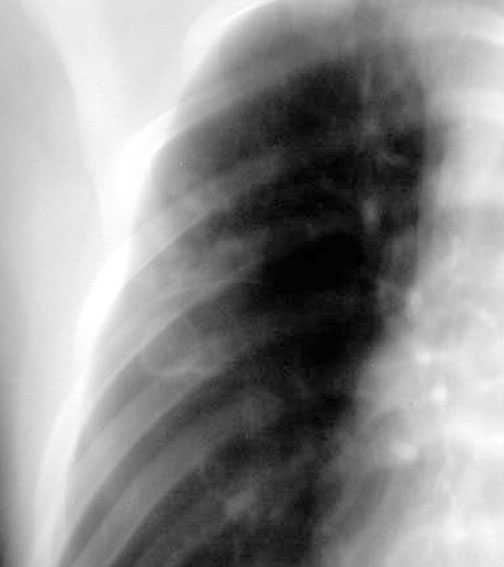

Case 30

Lateral

Initial PA

Initial lateral

Follow up

Labeled Image What are the common segments for aspiration lung abscess?

What are the types of aspiration?